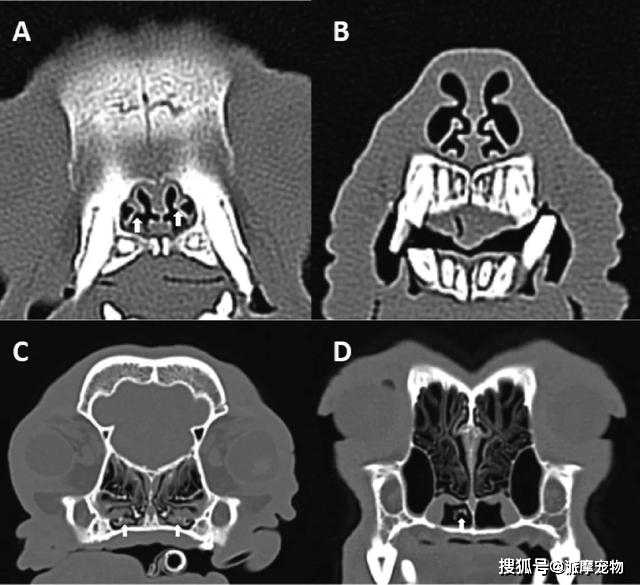

犬鼻部ct横切面